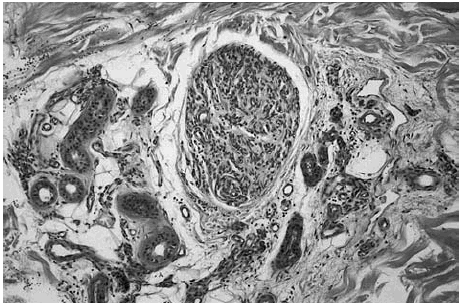

Se realizó una extirpación quirúrgica de la lesión. El estudio histopatológico mostró una tumoración dérmica multilobulillar con una zona central hipocelular, esclerosa y otra hipercelular en la periferia en la que se veían multiples espacios vasculares (fig. 2). Estas áreas más periféricas de espacios vasculares ramificados recordaban a un hemangipericitoma, y se continuaban insensiblemente con nódulos esclerosos. También se observaban nódulos hemangiopericitoides a distancia y sin conexión aparente con la tumoración principal (fig. 3).

Fig. 3.--Detalle de un nódulo de aspecto hemangiopericitoide que contiene múltiples espacios vasculares. Localizado a cierta distancia de la tumoración principal.